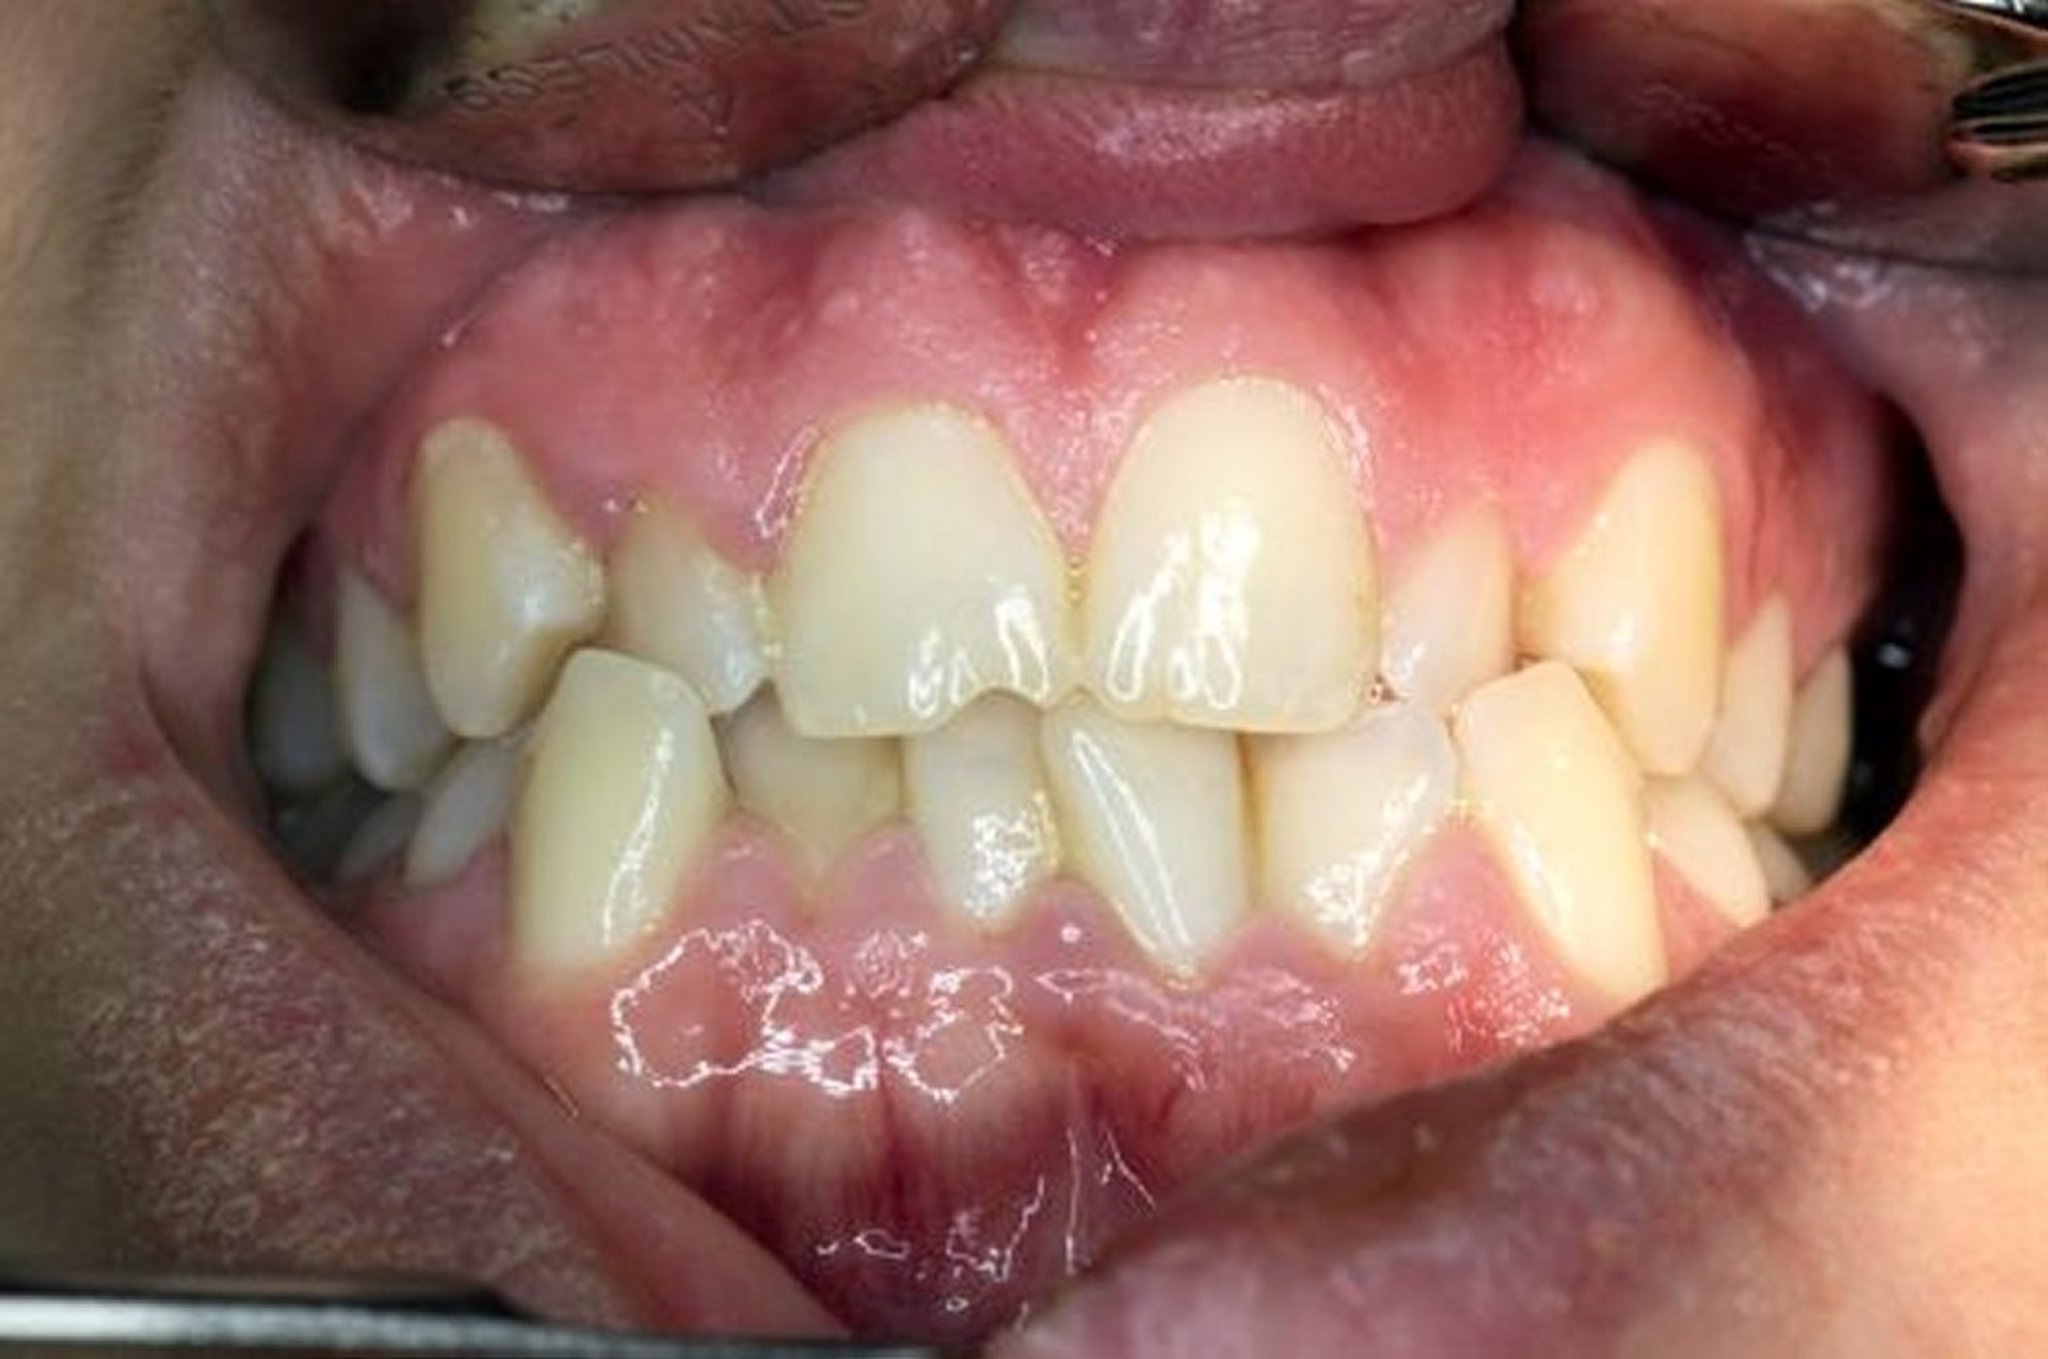

Maloklusi adalah keselarasan abnormal gigi dan kesesuaian posisi gigi atas dan bawah.

Biasanya, gigi atas sedikit tumpang tindih di luar gigi bawah. Tumpang tindih ini memungkinkan proyeksi (tampuk) pada setiap gigi masuk ke lekukan yang sesuai dari gigi yang berlawanan. Penyelarasan yang tepat membuat pengunyahan menjadi paling efektif dan juga mendistribusikan kekuatan pengunyahan secara merata. Mengunyah menghasilkan lebih dari 150 pound (1.000 kilopascal) gaya pada geraham dan mencengkam selama tidur menghasilkan 250 pound (1.700 kilopascal). Jika maloklusi menyebabkan kekuatan terdistribusi secara tidak merata, gigi dapat menjadi aus secara tidak normal, bagian mahkota dapat patah, dan gigi pada akhirnya dapat menjadi longgar.